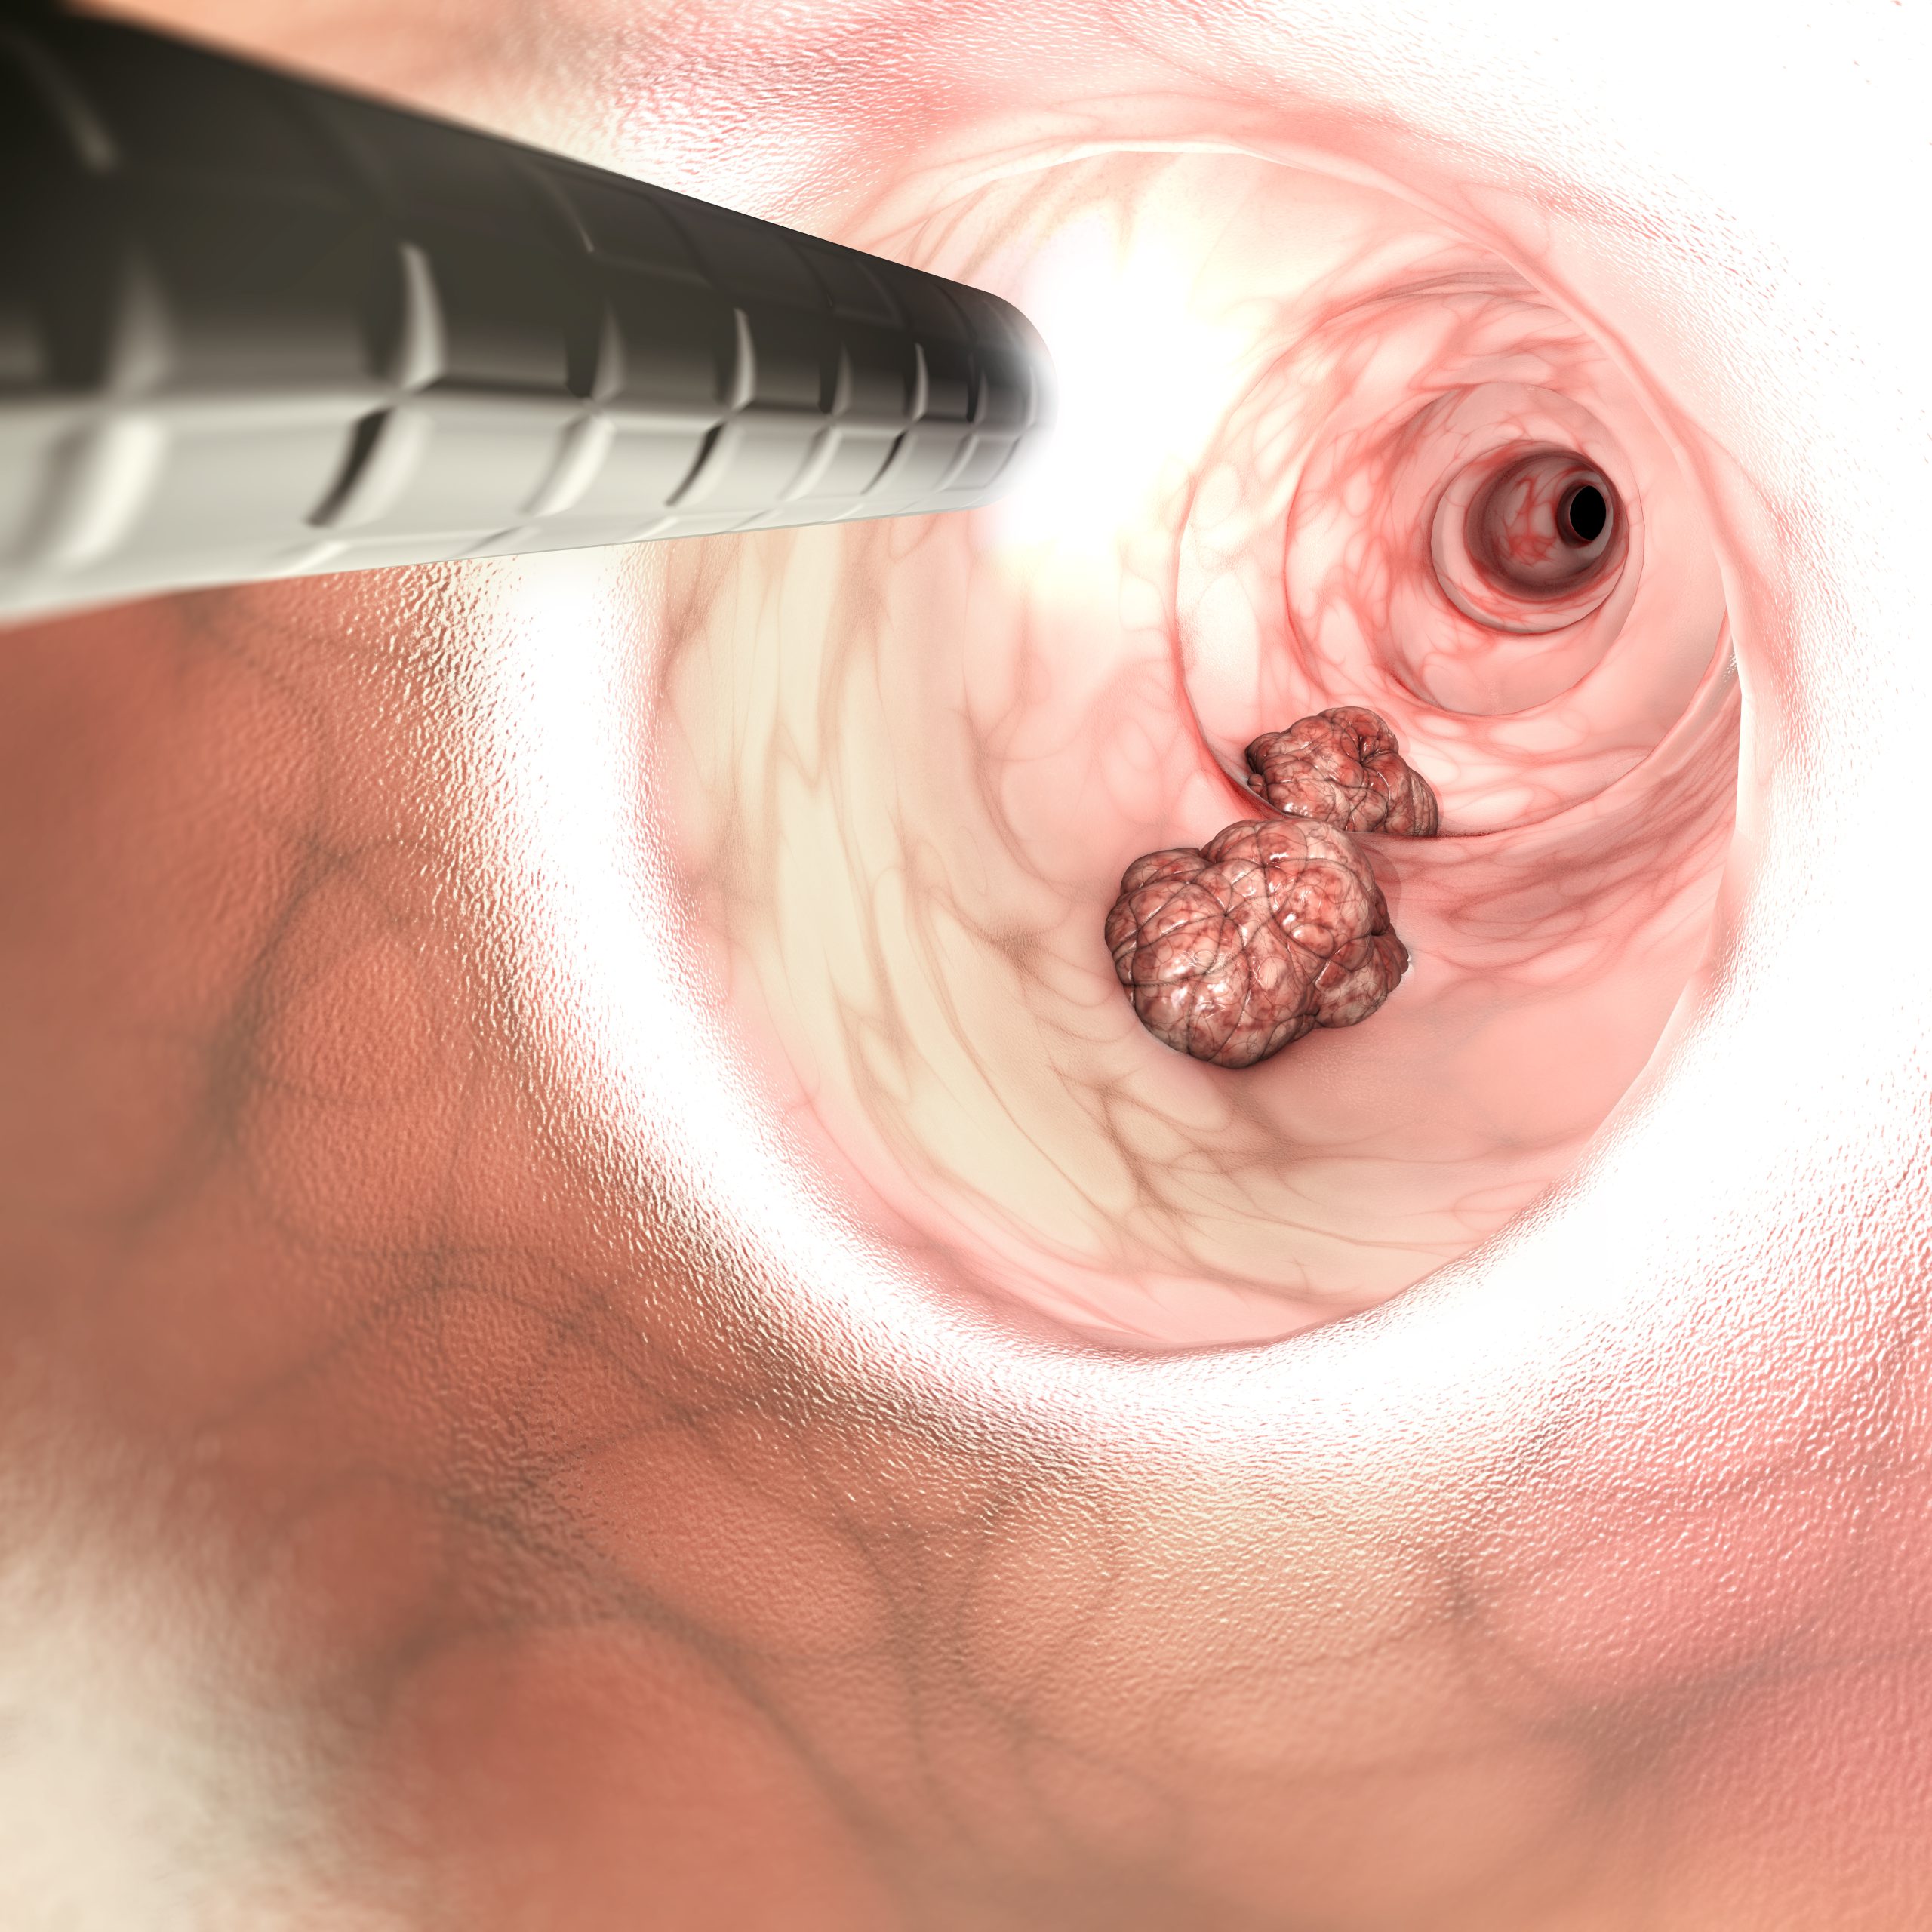

In order for treatment to be effective with long-term results, it must address the entire digestive tract, even the parts where the inflammation has not yet manifested. Whether the disease was diagnosed in the stomach, the small intestines or the large intestines, the treatment must include all these three sections. The reason for that is that while the inflammation has been diagnosed in just one area, it could be the result of a failure in another part of the digestive tract. Moreover, this diagnosed digestive disease might even be the result of a failure in other bodily systems altogether. Hormonal imbalance, malfunction of the hepatic system, thyroid malfunction, blood deficiency, improper blood circulation, etc., can all have a major influence on the digestive tract function. For example: chronic constipation can be the result of an out of synced action of the pelvic muscles relaxation and contraction during defecation. Another common example is stagnation of the liver, which often causes a deficiency in bile secretion, thereby, hindering the digestion of lipids.

The conventional classification does not differentiate between various stages of any digestive tract disease. Therefore, when applying treatment, the conventional classification does not take into account the severity or the extent of the damage to the particular diagnosed area of pathology in the digestive tract. The conventional treatment is the same, regardless of whether the pathology manifested is mild or severe. For example: peptic ulcer would be classified and treated the same, whether it is a minor inflammation in a small area of the stomach lining or an advanced bleeding ulcer with harsh symptoms – both of these cases would be classified as “peptic ulcer” and treated with the same chemical pills. Another common example is Crohn’s disease: in one case it could be in its initial stages, while another case could have advanced up to a bowel resection. Both of these cases would be classified as “Crohn’s disease” and treated the same.

For a successful treatment, there needs to be first a differential diagnosis in each and every case, regardless of other cases diagnosed in the same category by the conventional medicine. There could be hundreds of cases, all diagnosed as “Crohn’s”, but each one of them has a different pathological path and a different manifestation in terms of the inflammation site, the severity of the damage and the root causes for the inflammation. Furthermore, each and every case falling under the same convention category differs from all the other cases in its personal external and internal conditions, relating to the extent of the possible recovery and recovery speed. The lack of such a differential diagnosis, treating all cases as same, result in a failure to cure most chronic digestive tract diseases.